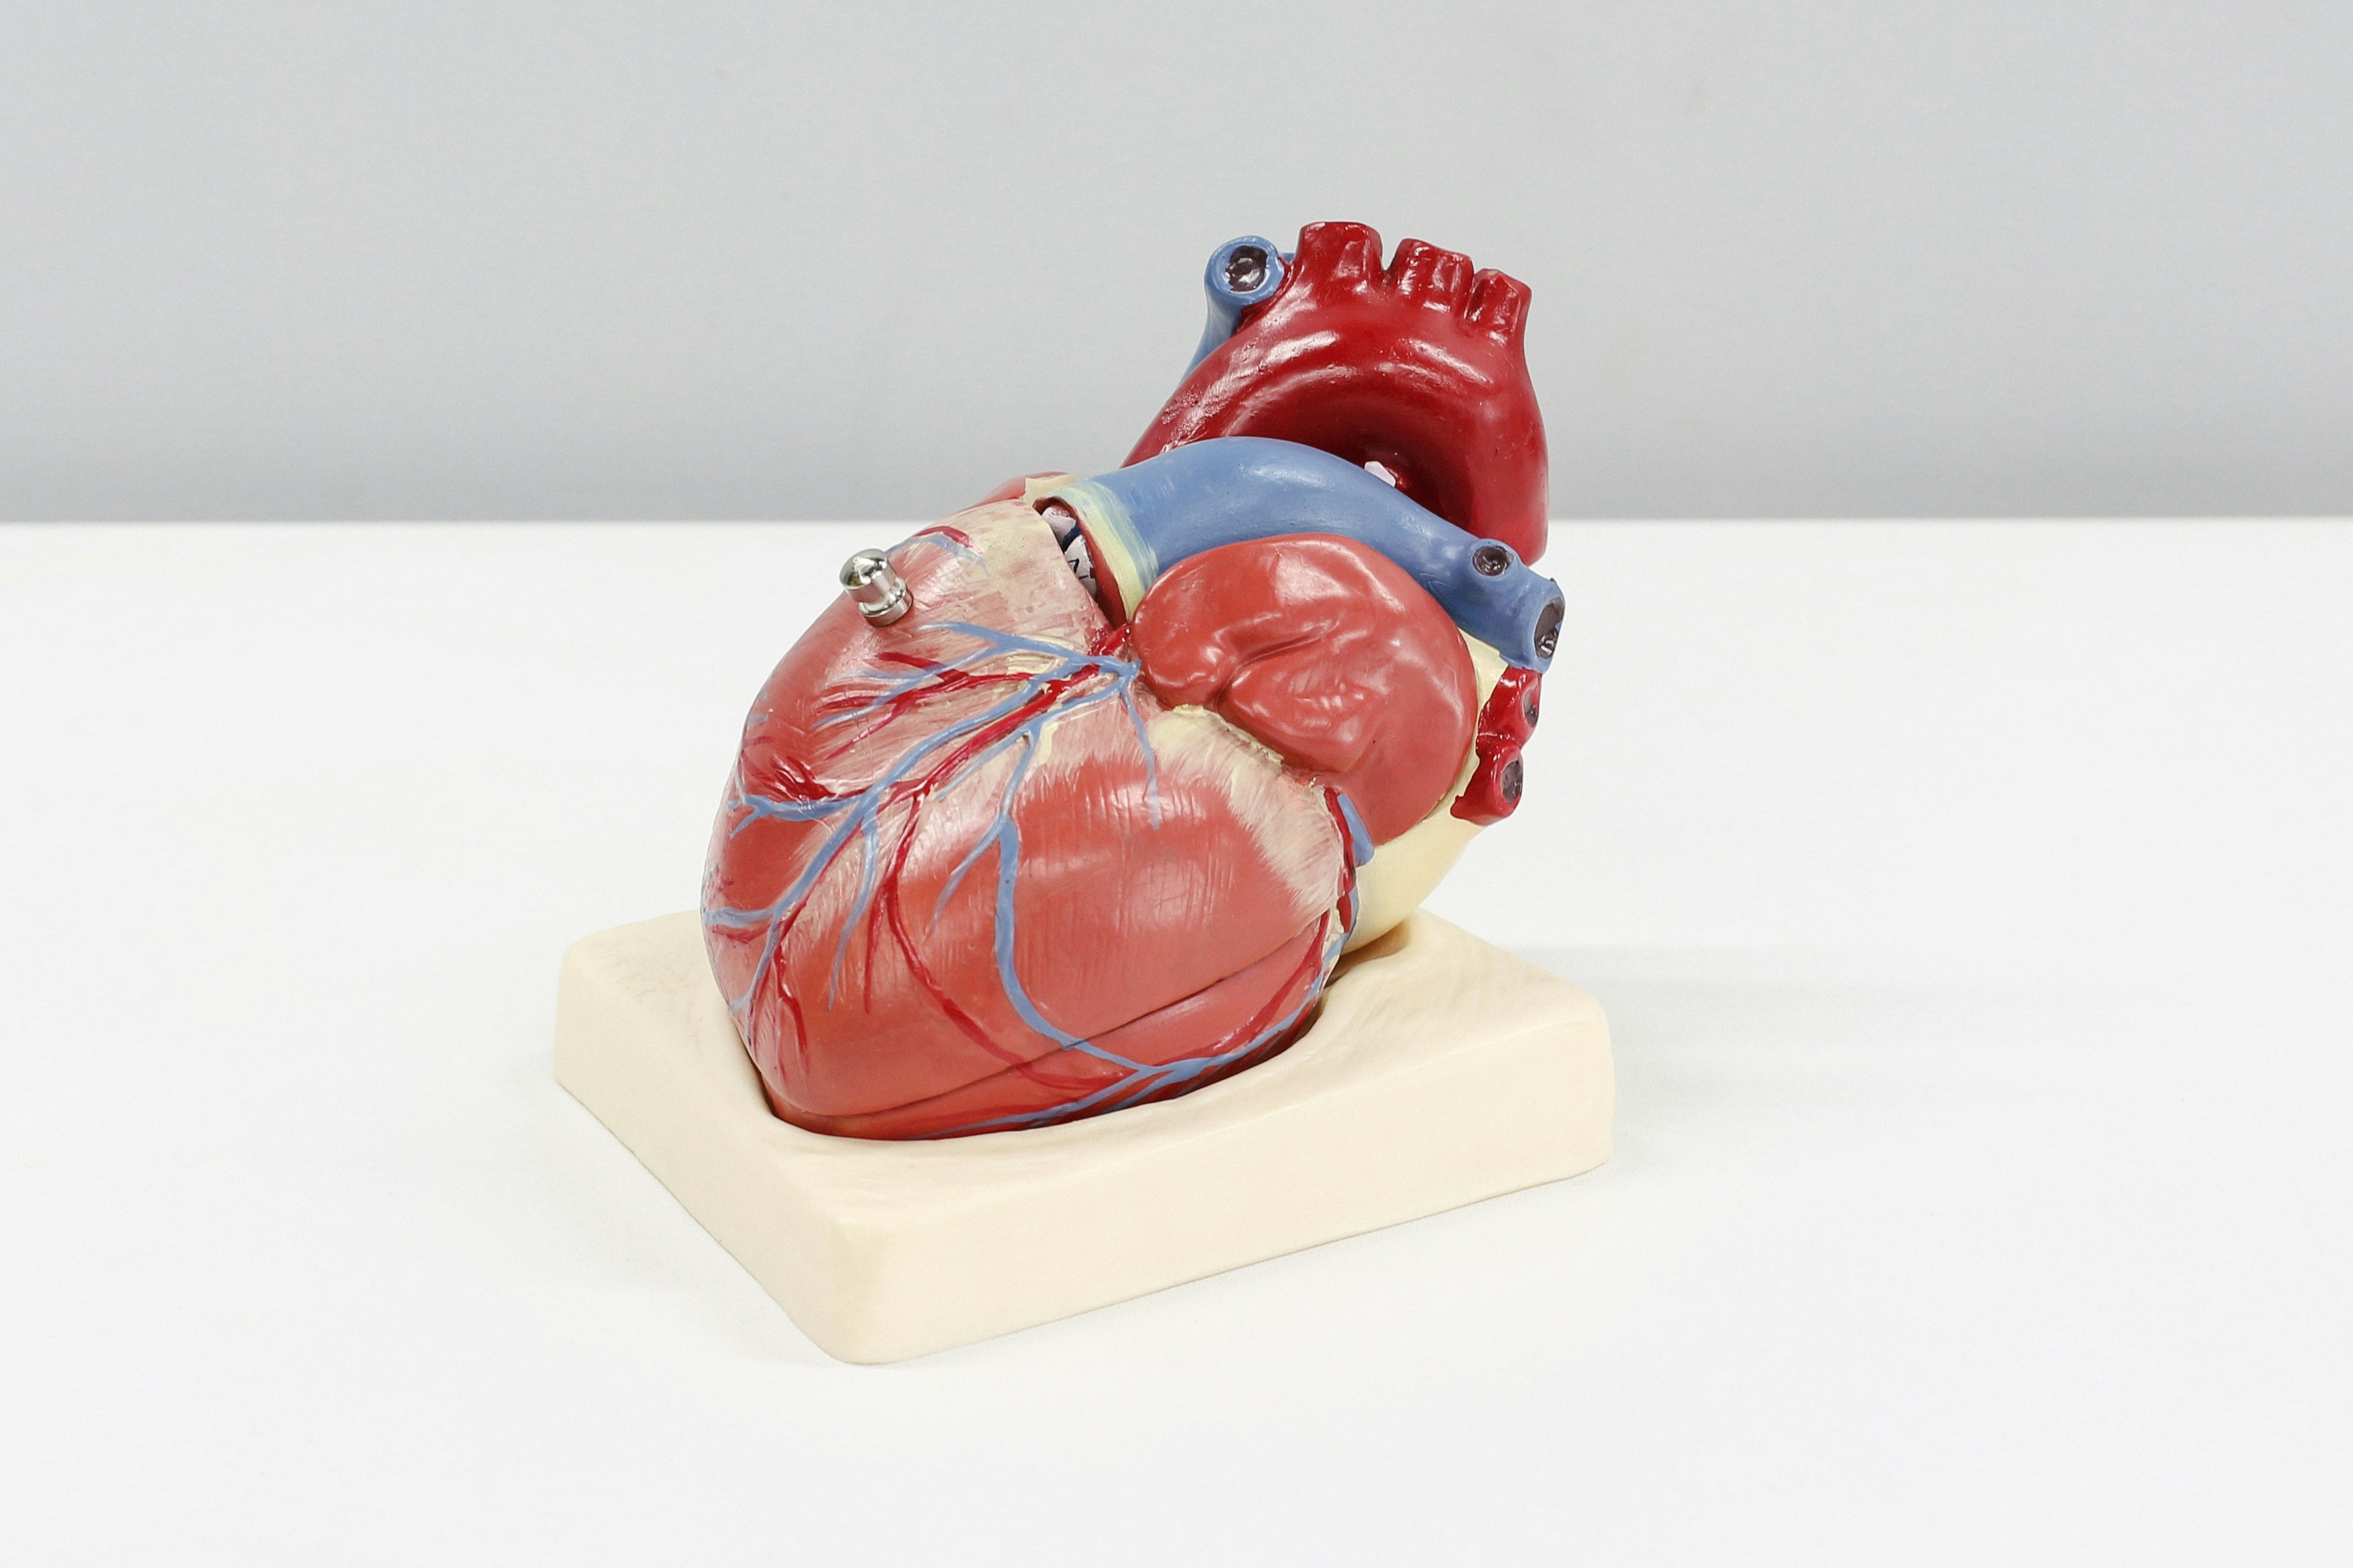

Koroner arter hastalığı, kalbi besleyen damarların daralması veya tıkanması sonucu kalbe yeterince oksijenli kan ulaşamaması durumudur. Bu durum, kalp...